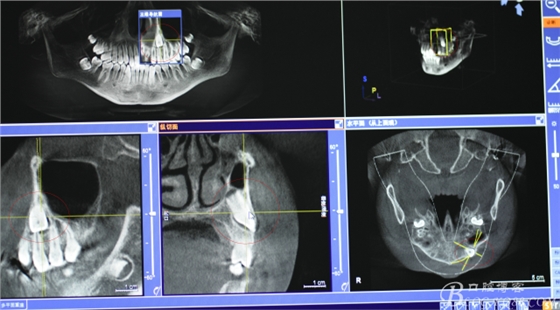

圖1.術(shù)前患者在當(dāng)?shù)嘏娜捌?,發(fā)現(xiàn)23位于24根尖部,經(jīng)正畸科會(huì)診,建議拔除23,遂拍cbct檢查:23牙冠騙近唇側(cè)。

圖2.冠向切面、23位于24根尖區(qū)、24牙根未見(jiàn)吸收